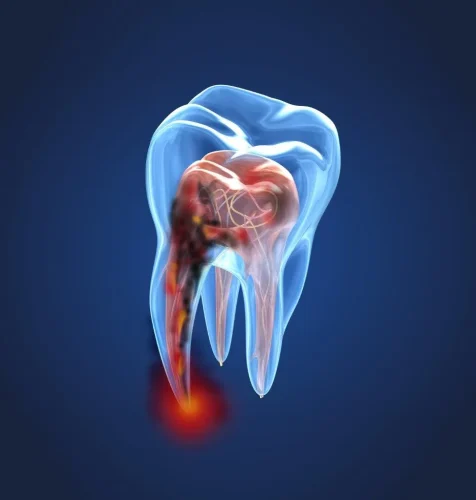

Trattamenti di endodonzia

Baldan Dr. Arianna Medico Odontoiatra esegue anche trattamenti di endodonzia: presso lo studio con sede a Mirano, in provincia di Venezia, abbiamo tutte le conoscenze e gli strumenti per salvare il dente in caso la carie degeneri fino ad attaccare la polpa dentaria.